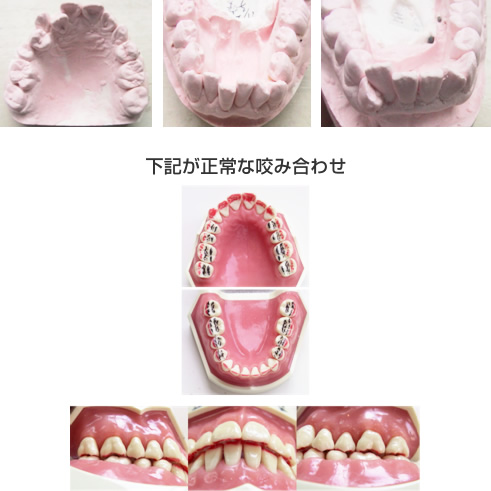

※黒い部分が咬み合わせせいていると良いです。赤い部分が当たっていると全身症状が出やすいです。

歯列不正に関しては歯磨きをしているつもりでも磨き残しが多く、虫歯や歯周病になる可能性が高くなります。

正常な状態は歯と歯の間に骨があります。

歯列不正で歯がひっつき歯と歯の間の骨がなくなります。

この状態をルートプロキシミティといいます。

歯と歯の間に骨がないので単純な歯周病(骨を腐らす病気)でもあっという間に重度歯周病になり、歯が抜けます。

ルートプロキシミティの状態だと歯と歯との間に骨がないので、単純な歯周病でもあっという間に重度歯周病になり歯が抜けてしまいます。

矯正をして歯並びを正常にすると病気も止まります。

そのため、歯列不正の方は歯を磨いても40歳~60歳というわかさで、歯が抜けることもあるのです。お金に変えられない歯を失わないためにも、早めに矯正治療を行って歯を残そうということなのです。

歯列不正が虫歯と歯周病の原因です。どれだけ歯を磨いても形態学的に汚れがたまりやすい為、虫歯や歯周病になります。その部分に差し歯をしても汚れがたまりやすい条件は改善されないので必ず再発しつづけます。